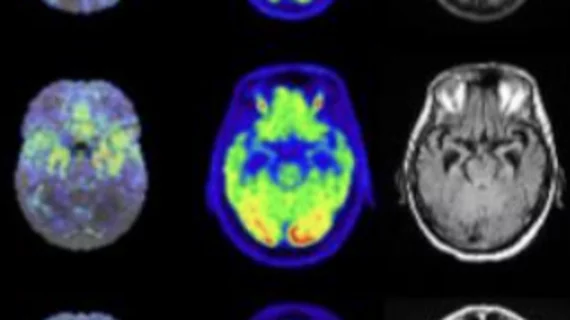

Physicians utilize medical imaging to see inside the body to diagnose and treat patients. This includes computed tomography (CT), magnetic resonance imaging (MRI), X-ray, ultrasound, fluoroscopy, angiography, and the nuclear imaging modalities of PET and SPECT.